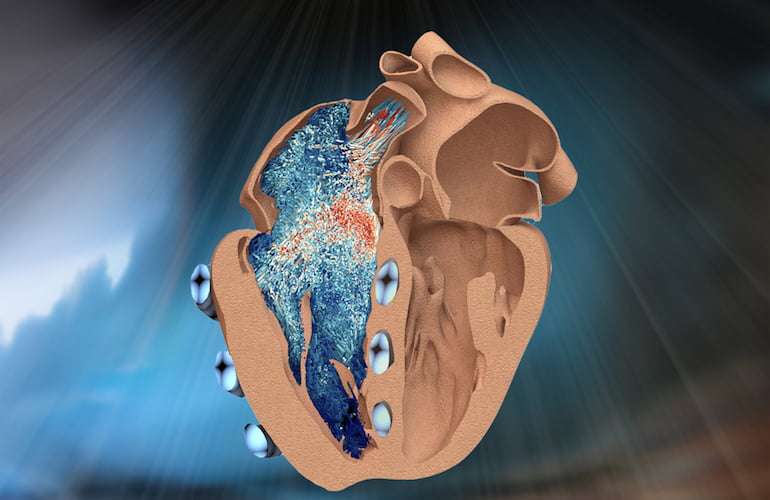

MIT engineers have developed a robotic replica of the heart’s right ventricle, which mimics the beating and blood-pumping action of live hearts. The robo-ventricle combines real heart tissue with synthetic, balloon-like artificial muscles that enable scientists to control the ventricle’s contractions while observing how its natural valves and other intricate structures function. The post MIT […]